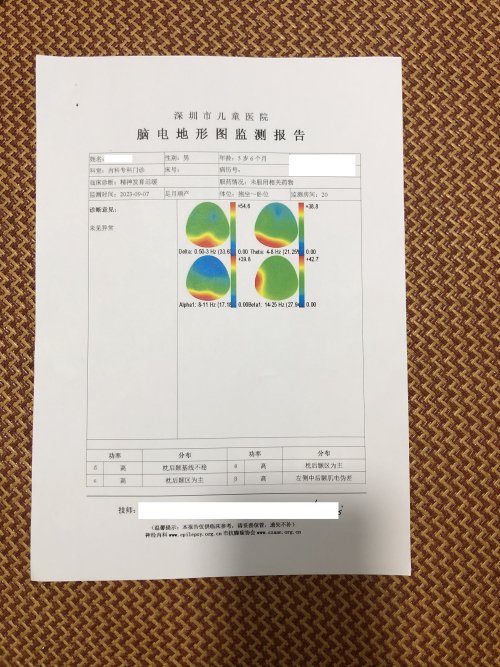

反馈下情况,孩子在国内的医院已经进行过一轮全面检测,没发现什么问题,但是现象是存在的。医生也没什么办法。医生说核磁共振和脑电图没问题,我们也不是很看得懂,各位如果懂的,请指点一下。另外进行了部分基因检测,没发现异常。下一步,我们国庆后打算去更权威的医院去碰碰运气。谢谢各位!

513.6 KB 查看: 103

532.8 KB 查看: 142

551 KB 查看: 132

526.8 KB 查看: 133

510 KB 查看: 103

506.4 KB 查看: 124

495.7 KB 查看: 165

435.1 KB 查看: 151